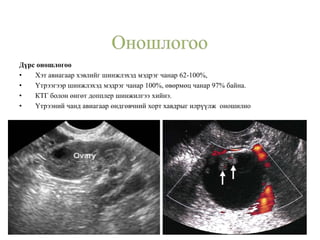

Дүрс оношлогоо

• Хэт авиагаар хэвлийг шинжлэхэд мэдрэг чанар 62-100%,

• Үтрээгээр шинжлэхэд мэдрэг чанар 100%, өвөрмөц чанар 97% байна.

• КТГ болон өнгөт допплер шинжилгээ хийнэ.

• Үтрээний чанд авиагаар өндгөвчний хорт хавдрыг илрүүлж оношилно

Дүрс оношлогоо • Хэтавиагаар хэвлийг шинжлэхэд мэдрэг чанар 62-100%, • Үтрээгээр шинжлэхэд мэдрэг чанар 100%, өвөрмөц чанар 97% байна. • КТГ болон өнгөт допплер шинжилгээ хийнэ. • Үтрээний чанд авиагаар өндгөвчний хорт хавдрыг илрүүлж оношилно